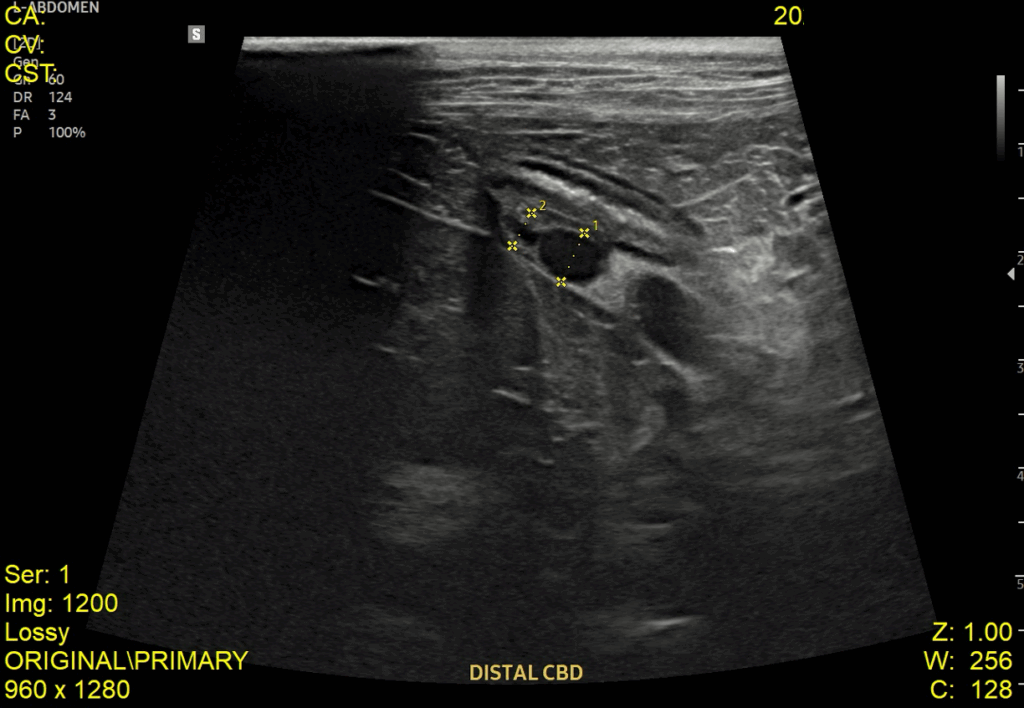

이어서 진행한 복부 초음파 검사에서는 췌장염 소견과 함께 위벽 및 일부 장 근층 비후가 관찰되었고, 담낭관(Cystic duct)과 총담관(CBD)이 심하게 확장되어 있으며 내강 내 슬러지가 확인되었습니다. 또한 담낭 내에는 중등도의 슬러지와 담석이 있었고, 간 내 담도 결석과 전반적인 간 에코 증가도 함께 확인되었습니다.

내원당시 복부초음파 검사 결과 / 출처: 강서YD동물의료센터